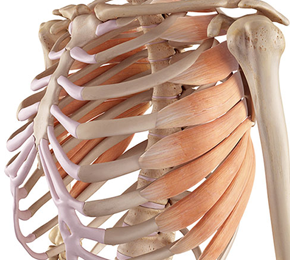

갈비뼈 근처에 존재하는 많은 근육과 인대 부위에 경미하였거나 그렇지 아니하면 너무한 손상, 염증, 파열 등이 일어난 상태를 늑골 염좌, 갈비뼈 염좌라고 부릅니다 각별히인대의 손상 정도에 따라 과도한 멍, 붓기, 통증이 결성되며 완전한 파열이 발생되었을 때에는 작열감, 숨 쉴 때 불편감이 심할 수 있고요.

오른쪽 갈비뼈 아래 통증 원인 - 근육 긴장

갈비뼈를 연결하는 늑간근의 근육 긴장이나 부상은 갈비뼈 오른쪽에 통증을 발생시킬 수 있다고 합니다. 이 통증은 날카롭거나 둔할 수 있기도하고 움직이거나 심호흡을 하다가 보면 안좋아질 수 있다고 합니다. 근육 긴장은 갑작스러운 뒤틀림이나 들어 올리기, 가슴 근육의 많은 사용 또는 부때맞은 들어 올리기 기술로 인해 발생할수 있습니다.